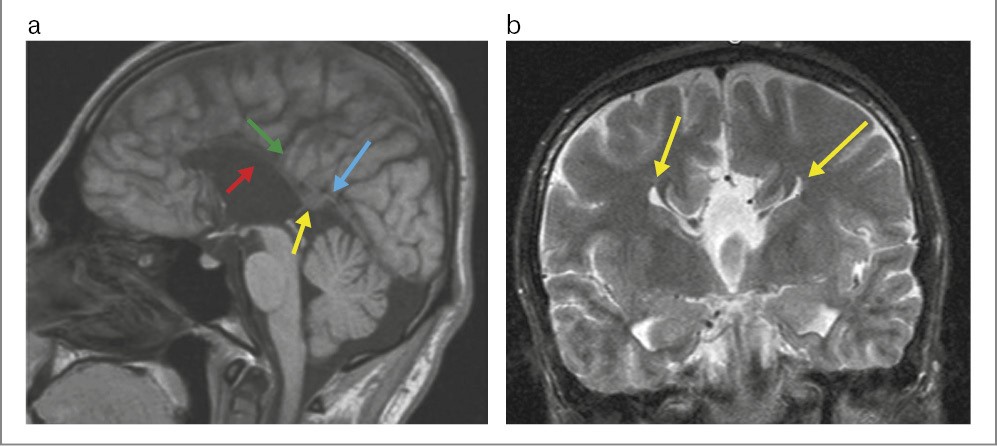

На серии Т1–Т2-взвешенных томограмм в сагиттальной, аксиальной и коронарной проекциях получены изображения ГМ. Очаговых и диффузных изменений вещества ГМ не выявлено.

В срединной сагиттальной проекции МТ и прозрачная перегородка, равно как и комиссуры, не визуализируются. Определяется расширение крыши III желудочка, к которому спускается межполушарная борозда. Имеется аномальная поясная извилина. Медиальная борозда имеет спицевидную форму.

Визуализируются миелинизированные пучки Пробста. Гиппокамп закруглен в аксиальных срезах.

Боковые желудочки параллельные, ассиметричные, расширены за счет задних рогов в наибольшем измерении: правый – до 35 мм, левый – до 25 мм без перивентрикулярной инфильтрации, III и IV желудочки не расширены.

Передние рога латеральных желудочков имеют вертикальный ход, длина правого и левого составляет 17 и 16 мм соответственно.

Миндалины мозжечка расположены на уровне большого затылочного отверстия, не выступая за его пределы.

Заключение: МРТ-картина полной АМТ и прозрачной перегородки (рис. 4).

Рис. 4. Больная К., 13 лет. МРТ ГМ: a – Т1-взвешенное последовательное изображение в сагиттальной плоскости: полное отсутствие МТ (голубая стрелка); расширение крыши III желудочка (красная стрелка); аномальная поясная извилина (желтая стрелка); b – Т2-взвешенное последовательное изображение в коронарной плоскости. Симптом «шлем викинга» – поясная извилина вывернута в виде суженных и удлиненных лобных рогов (голубые стрелки); c – Т2-взвешенное последовательное изображение в аксиальной плоскости: симптом «гоночного автомобиля» – расширенные латеральные желудочки, правый – до 35 мм, левый – до 25 мм (желтые стрелки).

Консультирована неврологом, по результатам обследования которого выявлено, что рефлексы не нарушены, имеются выраженные расстройства аутистического спектра, нарушение речевого развития, когнитивный дефицит в виде тяжелой умственной отсталости. При ЭЭГ достоверных изменений эпилептиформного характера не выявлено.

На основании изложенного поставлен окончательный диагноз «сочетанная полная АМТ с агенезией прозрачной перегородки, тяжелая умственная отсталость, ассоциированная с эпилепсией».